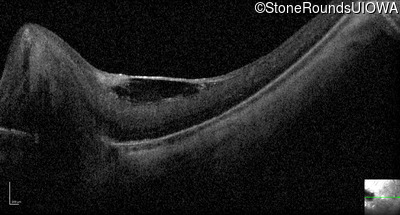

Optical Coherence Tomography - Right - 20/125

Exemplar